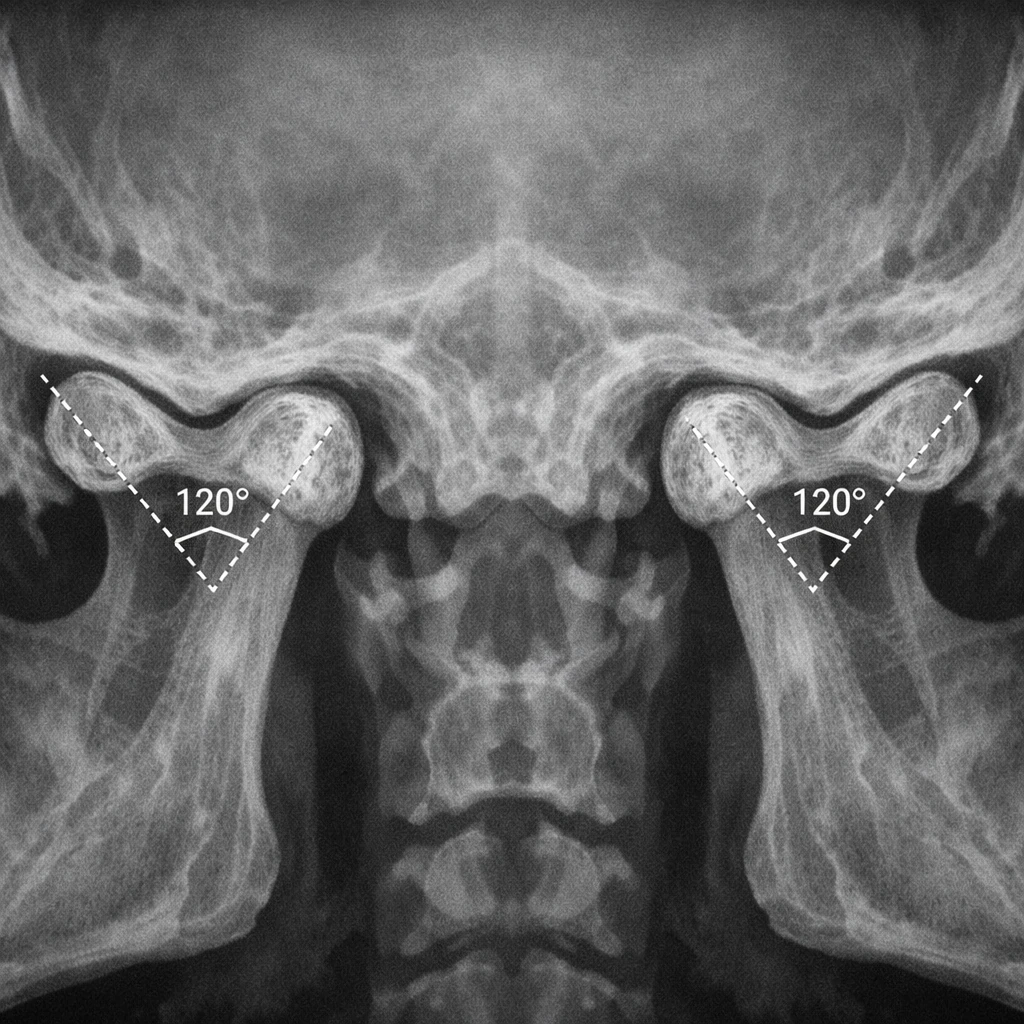

ارتباط اجزای استخوانی TMJ با تصویربرداری

برای بررسی اجزای استخوانی مفصل گیجگاهی فکی، CT Scan بهترین روش تصویربرداری محسوب می‌شود. در مقابل، MRI بیشتر برای بررسی دیسک مفصلی و بافت‌های نرم کاربرد دارد.

در CT اسکن می‌توان شکل کندیل، تقارن دو طرف، زاویه کندیلی و تغییرات دژنراتیو استخوانی را به‌خوبی ارزیابی کرد.

TMJ CT scan condylar angle 120 degrees